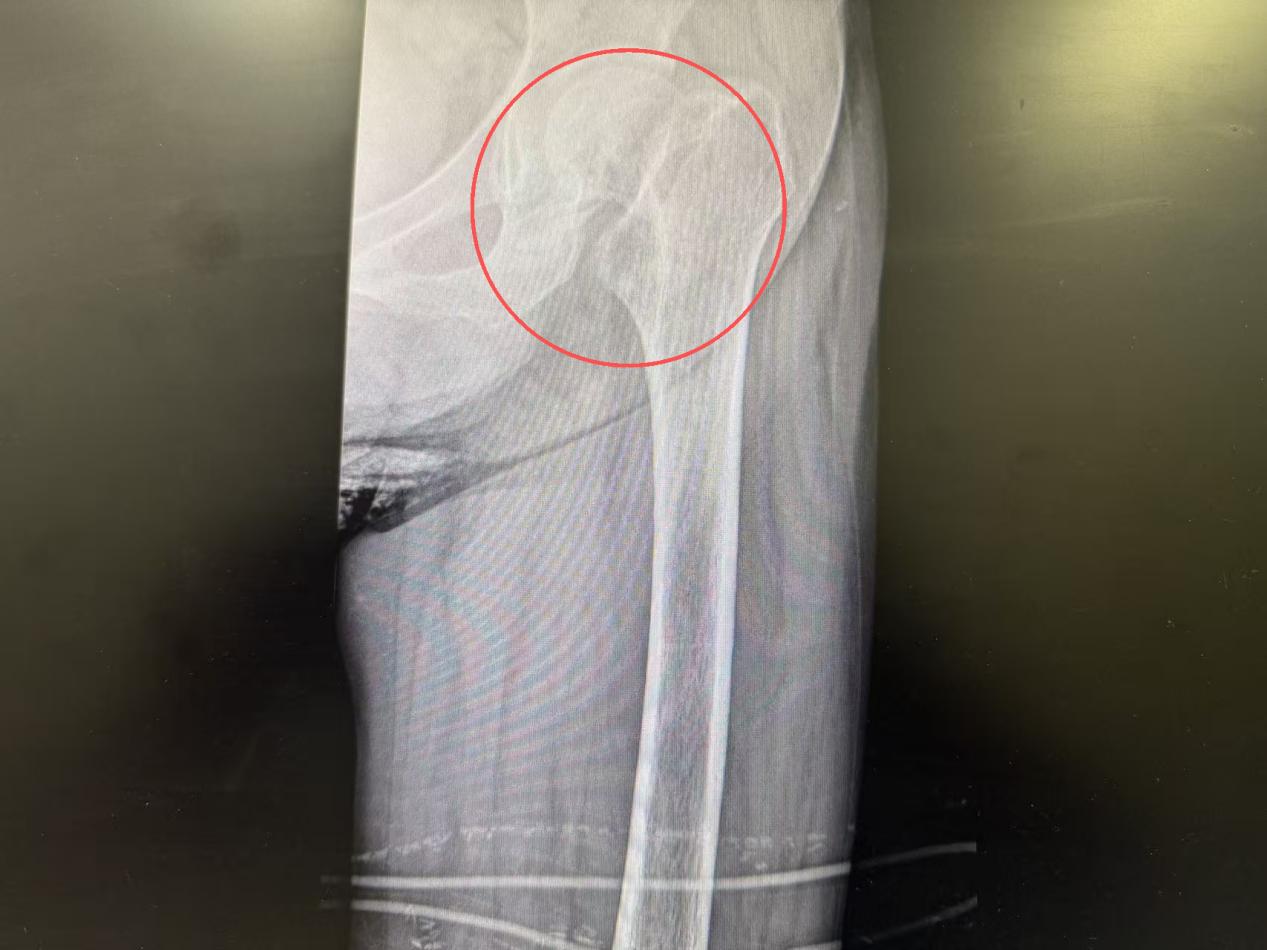

图为术前

检查结果触目惊心:左侧股骨颈骨折、重度骨质疏松、2型糖尿病、双侧多发肋骨骨折,还伴有陈旧性脑梗死、脑萎缩、间质性肺炎等多种基础疾病。更棘手的是,长期卧床与糖尿病交织,导致血糖失控、肺功能恶化,将老人推向了危险边缘。